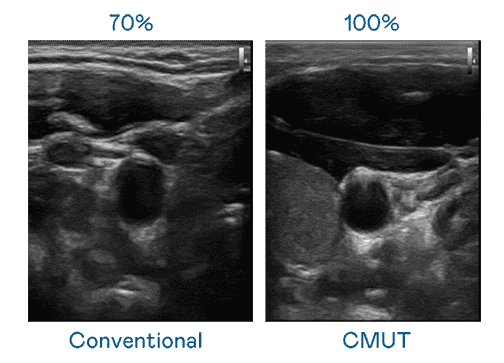

CMUT 技术是一种用电容式微机电元件来产生超音波讯号的技术。。。。与传统 PZT 压电式技术相比,,,CMUT 频宽增加 30%,,,,更宽频的超音波讯号让影像解析度大幅提升,,,是实现高影像品质医疗超音波扫描、、、促进精准医疗发展的关键技术。。。。

大频宽带来超清晰影像

超音波影像的解析度高低,,,,首先取决于探头能发出的讯号频宽。。。。william威廉中文官网 CMUT 可提供高清晰的超音波讯号,,提供高频宽、、、、高灵敏度、、、影像纹理细节更高的超音波影像,,协助医护人员缩短影像判读时间及利用精准的医疗影像进行诊断。。。。